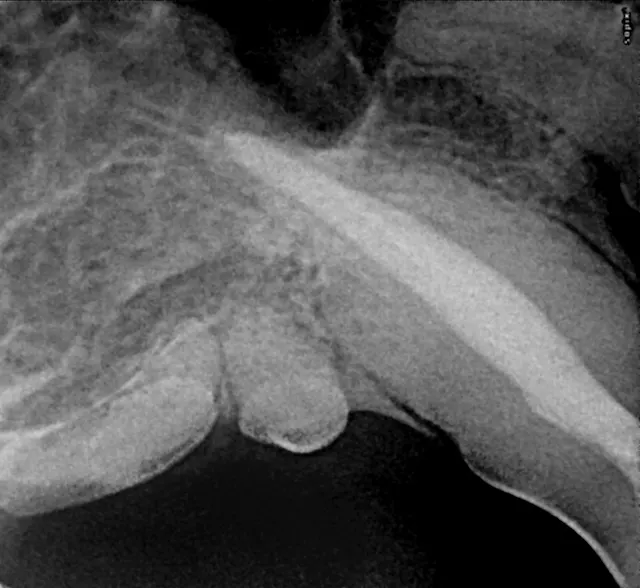

Intraoral radiograph of the rostral mandibles revealing advanced external resorption affecting both canine teeth

Appropriate therapy for tooth resorption will depend on clinical and radiographic appearance, as well as owner preference once treatment options have been discussed. Intraoral radiography is central to the decision-making process; if intraoral radiography is unavailable and tooth resorption is clinically apparent, the patient should be referred. If referral is not an option, the tooth should be extracted to eliminate oral bacterial invasion. Without intraoral radiography, root fragments may be left behind during extraction, potentially causing painful problems later.